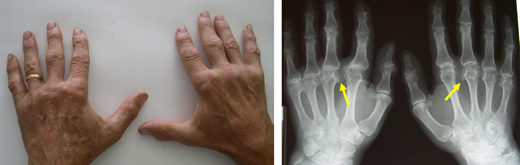

The index patient had a 62-year-old brother living in a rural area whose test results indicated C282Y homozygosity. His biochemical profile showed ferritin level, 1020  mg/L; TSAT, 78%; and a mild elevation of transaminases. Two years before, he had received a diagnosis of seronegative undifferentiated arthritis with poor response to hydroxychloroquine. A physical examination and plain radiogram showed typical hemochromatosis arthropathy of the hands (Figure 5). The Fib-4 score and FibroScan confirmed the high probability of ALF,25 making a liver biopsy unnecessary. There were no clinical or biochemical signs of other relevant complications. Phlebotomy, surveillance for HCC, and physiotherapy of involved joints were started.

Figure 5.

Hemochromatosis arthropathy. Typical bilateral involvement of the metacarpophalangeal joints, especially the second and third, with plain radiogram showing the classical “hook” osteophytes. Hemochromatosis arthropathy can involve multiple other joints, including the hip, ankle, knee, elbow, shoulder, and spine.